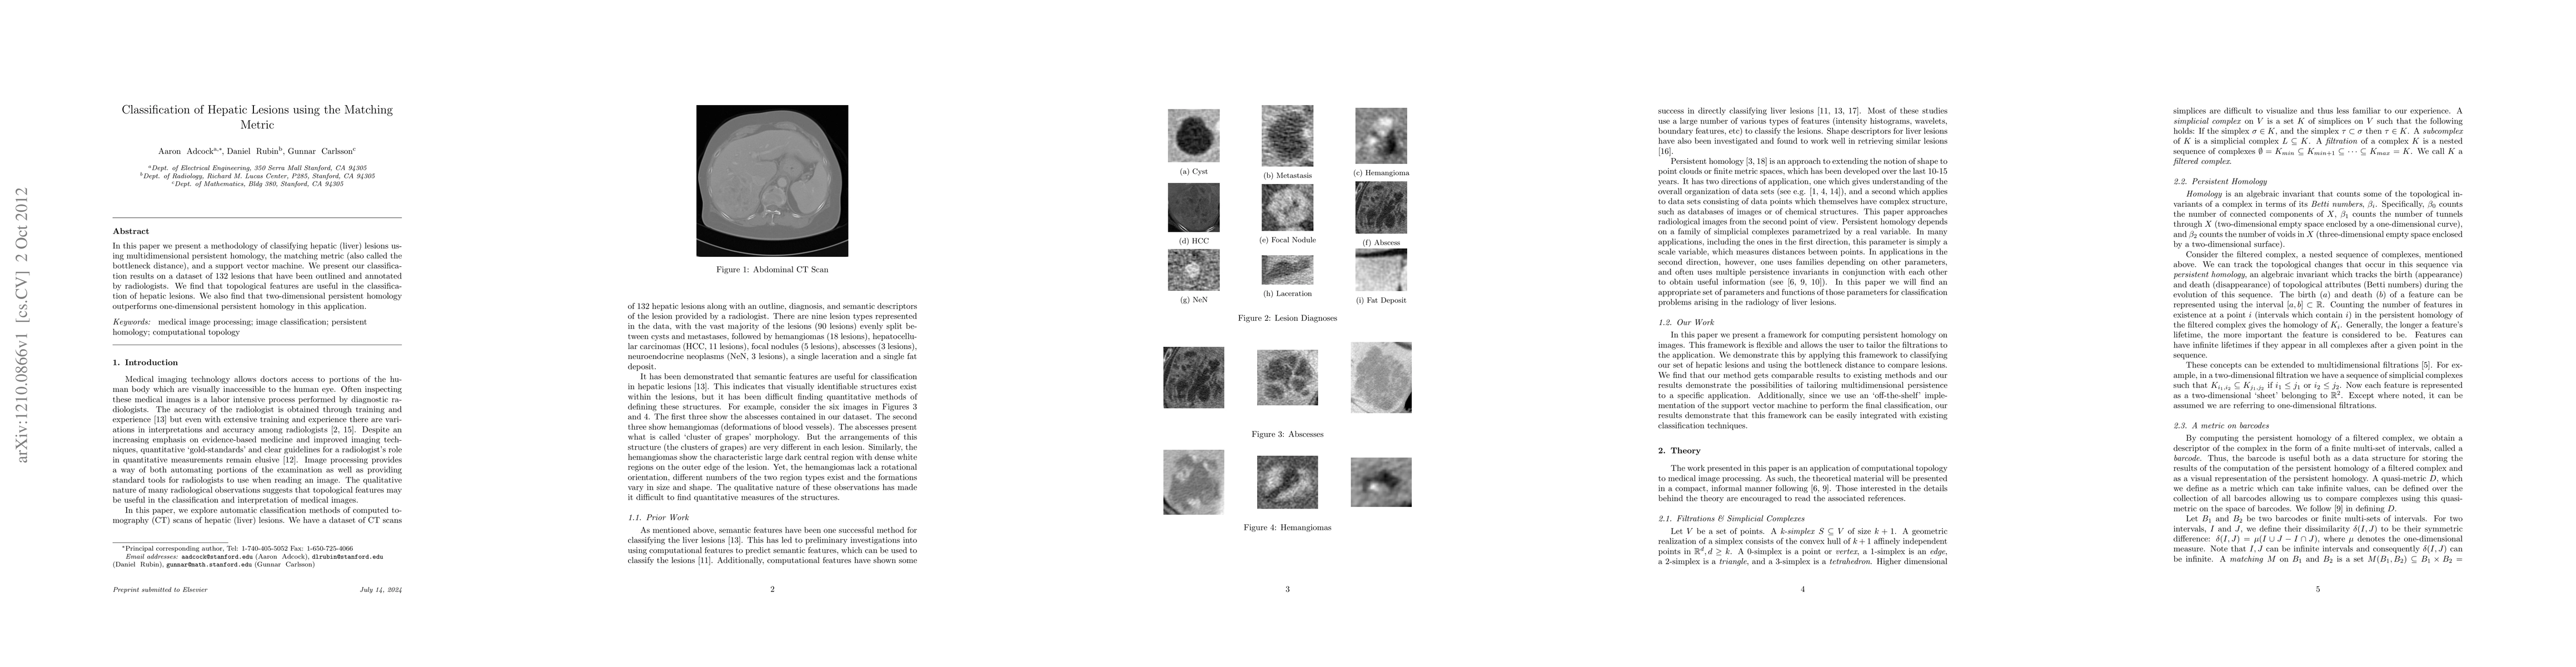

In this paper we present a methodology of classifying hepatic (liver) lesions using multidimensional persistent homology, the matching metric (also called the bottleneck distance), and a support vector machine. We present our classification results on a dataset of 132 lesions that have been outlined and annotated by radiologists. We find that topological features are useful in the classification of hepatic lesions. We also find that two-dimensional persistent homology outperforms one-dimensional persistent homology in this application.

The paper presents a methodology for classifying hepatic lesions using multidimensional persistent homology, the matching metric (bottleneck distance), and a support vector machine (SVM). The approach involves forming simplicial complexes from 2D liver images, creating filtrations based on pixel intensity and distance from the lesion border, computing persistent homology barcodes, and using the matching metric to compare lesions. Finally, a feature vector is generated using the barcode distances, which is then fed into an SVM for classification.